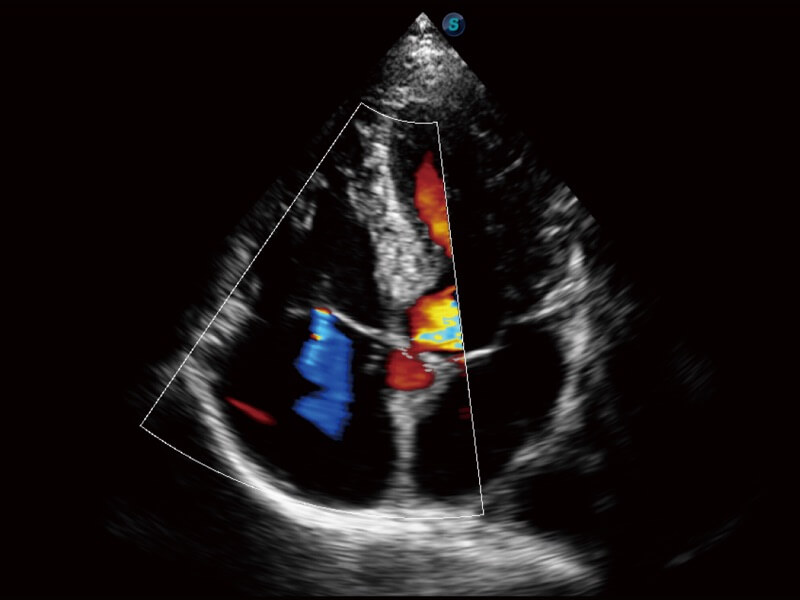

Ultraschall wird immer vielseitiger und übernimmt immer mehr klinische Aufgaben. Als Vorreiter, der Ärzten dabei hilft, mehr zu erreichen, ist ELITE mit einer umfassenden Palette fortschrittlicher Funktionen für die Allgemeine Bildgebung, Gynäkologie/Geburtshilfe, Kardiologie und mehr integriert.

Ultraschall wird immer vielseitiger und übernimmt immer mehr klinische Aufgaben. Als Vorreiter hilft ELITE den Ärzten dabei, mehr zu erreichen, indem es mit einer umfassenden Palette fortschrittlicher Funktionen ausgestattet ist, die die allgemeine Bildgebung, die Geburtshilfe/Gynäkologie, die Kardiologie und vieles mehr abdecken.